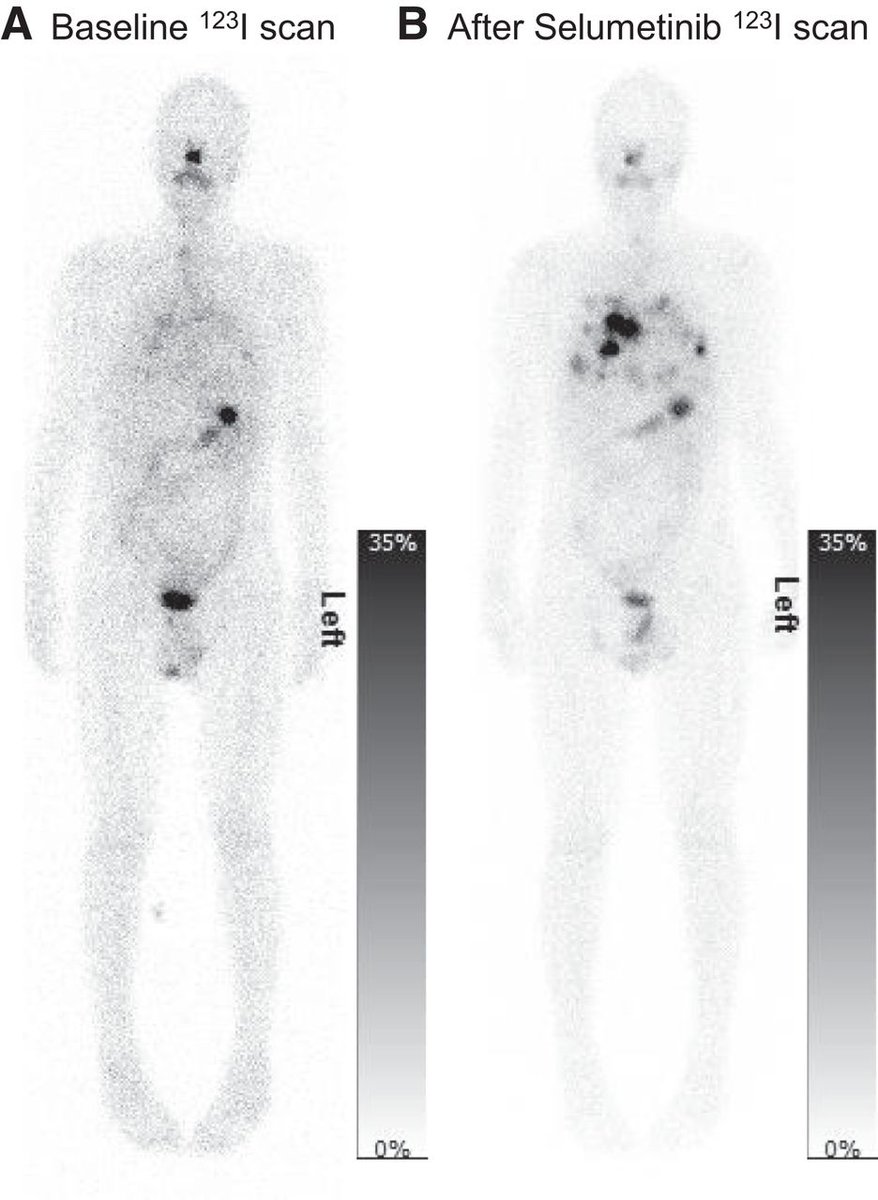

Pretherapy imaging and dosimetry offer personalized treatment planning for #ThyroidCancer patients, according to new research published in @JournalofNucMed ow.ly/PO1K50OUMiC